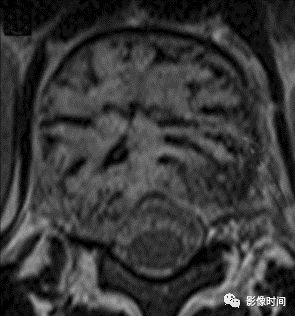

14微脑征

微脑(mini brain)征

本征象指在 MRI 横轴面图像上,病变残存的骨嵴形成曲线状的低信号结构向破坏区延伸,犹如深入脑回的脑沟。多见于椎体孤立性浆细胞瘤。

典型病例

病例 1. 37 岁女性,孤立性浆细胞瘤。横轴位 FSE T2WI 像示椎体信号异常,可见多发条状低信号伸入病变,类似脑沟(箭示)。

病例 2. 60 岁女性,椎体浆细胞瘤。横轴位 FSE T2WI 像示椎体内信号异常,低信号骨嵴伸入病变,其形态似「微脑/迷你脑」。

引用文献:Major NM,Helms CA.The "mini brain": plasmacytoma in a vertebral body on MR imaging.AJR Am J Roentgenol 2000;175:261-263.